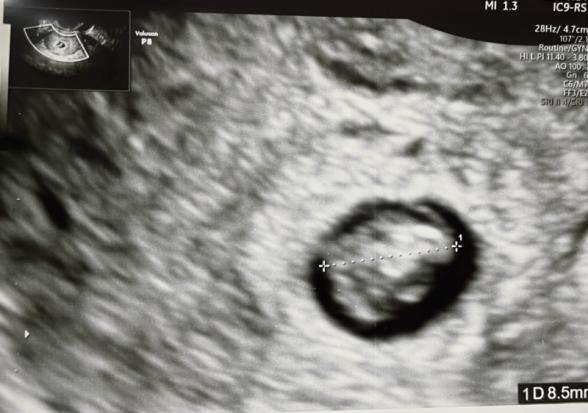

本日診察して頂いたら、赤ちゃんは8.5ミリで先週より5.5ミリ成長していたのですが、胎嚢に余裕がありません。心拍は6週から確認できています。

診察では胎嚢の大きさは一度も測られておらず、大きさはわかりませんが、おそらく先週とさほど変わらない気がします。